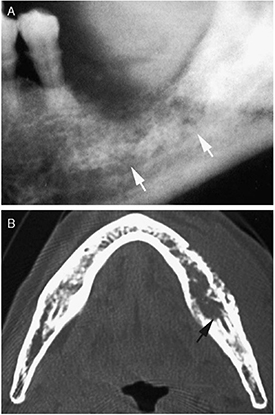

In CT, x-ray image slices are acquired at several different angles to reconstruct a tomographic image of the body. Each image slice is created by measuring x-ray attenuation through the tissue. CT is used for oral cancer diagnosis in evaluating the extent of infiltration in the buccal space, bone invasion, and extension to the retromolar trigone (figure 3) [8, 105–107]. Several studies have confirmed that CT is reliable in staging malignancy and detecting bone erosion [105, 106, 108]. Mukherji et al demonstrated that CT detected mandibular bone invasion with 96% sensitivity and 87% specificity [106]. Brockenborough et al reported diagnostic values in close range (95% sensitivity and 79% specificity) [109]. In addition, Trojanowska et al showed promising results using CT perfusion imaging to discriminate between benign and malignant lesions [110]. CT can thus be used as a diagnostic tool for evaluating symptomatic patients.

Figure 3. X-ray radiography (A) and CT image (B) of bone invasion (indicated by the arrows) caused by carcinoma of the mandibular gingiva. Reprinted from [107], Copyright (2009), with permission from Elsevier.

Standard image High-resolution imageAlthough CT effectively assessed tumor bone invasion at the advanced stages, it did not provide additional information to clinical examination for tumors less than 2 cm without bone involvement, rendering CT limited for early detection [105]. Further, CT is inadequate in characterizing soft tissues in the oral cavity, and image artifacts due to metallic dental fillings hamper adequate diagnosis [8, 111].